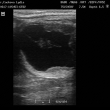

Preovulační folikul

embryo kolem 21.dne

Embryo 31. den